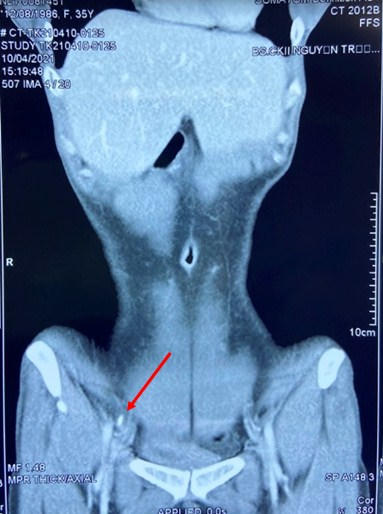

Vị trí dị vật (mũi tên đỏ) trên phim CT scan của người bệnh. Ảnh BVCC